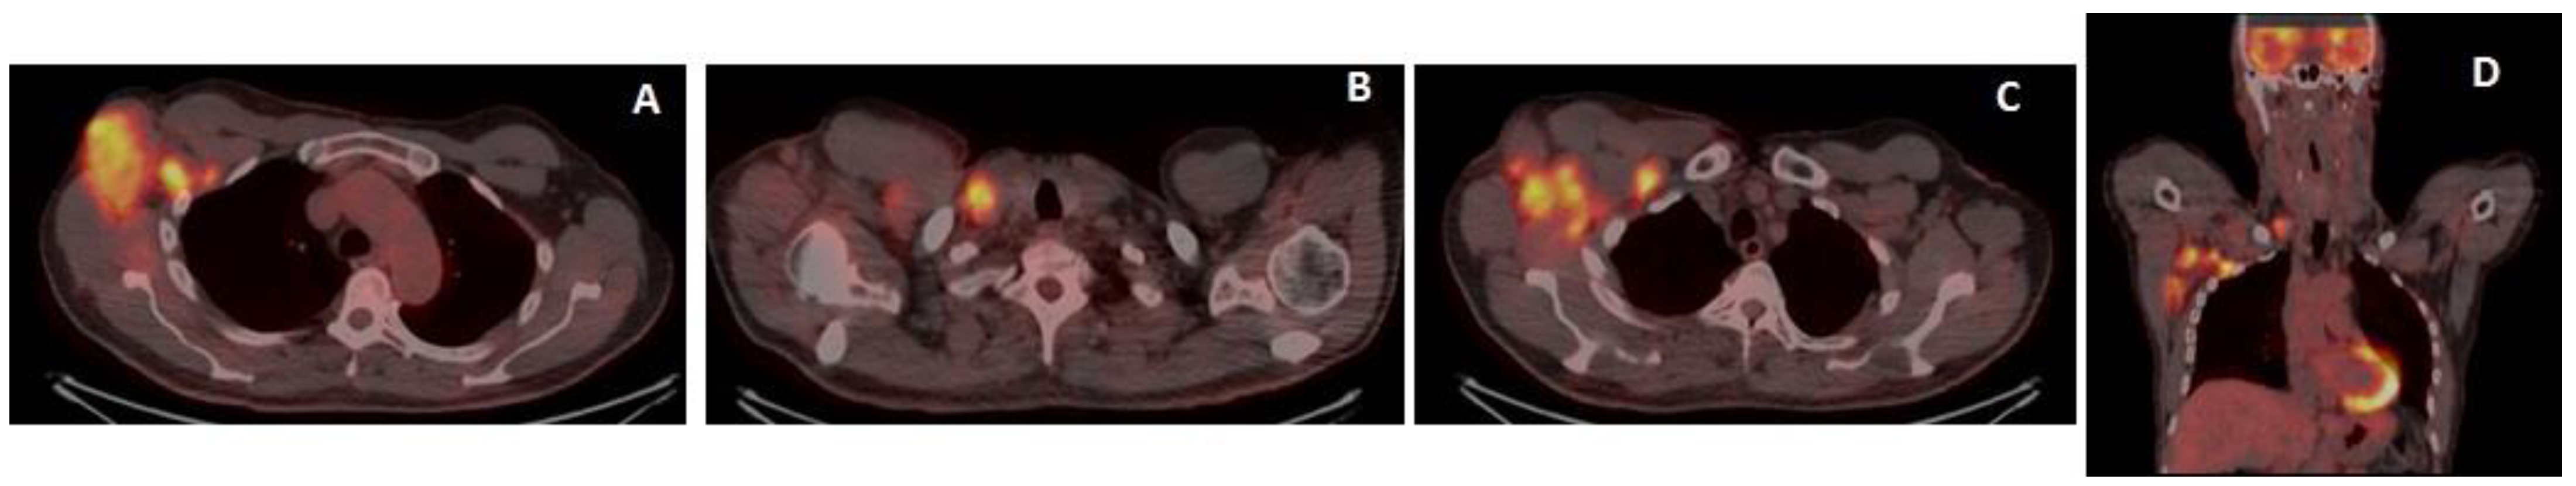

18F-Fluorodeoxyglucose positron emission tomography/CT (18-FDG-PET/CT) showed increased tracer uptake in the right axillary adenopathy, in the right supraclavicular adenopathy and in multiple axillary adenopathies (Figure 5).

Figure 5.

18-FDG-PET/CT at baseline (axial and coronal sections), increased tracer uptake in the right axillary adenopathy mass (SUV max 9.7) (A), in the right supraclavicular adenopathy (SUV max 7.6) (B) and in multiple axillary adenopathies (level I–III) (C,D).